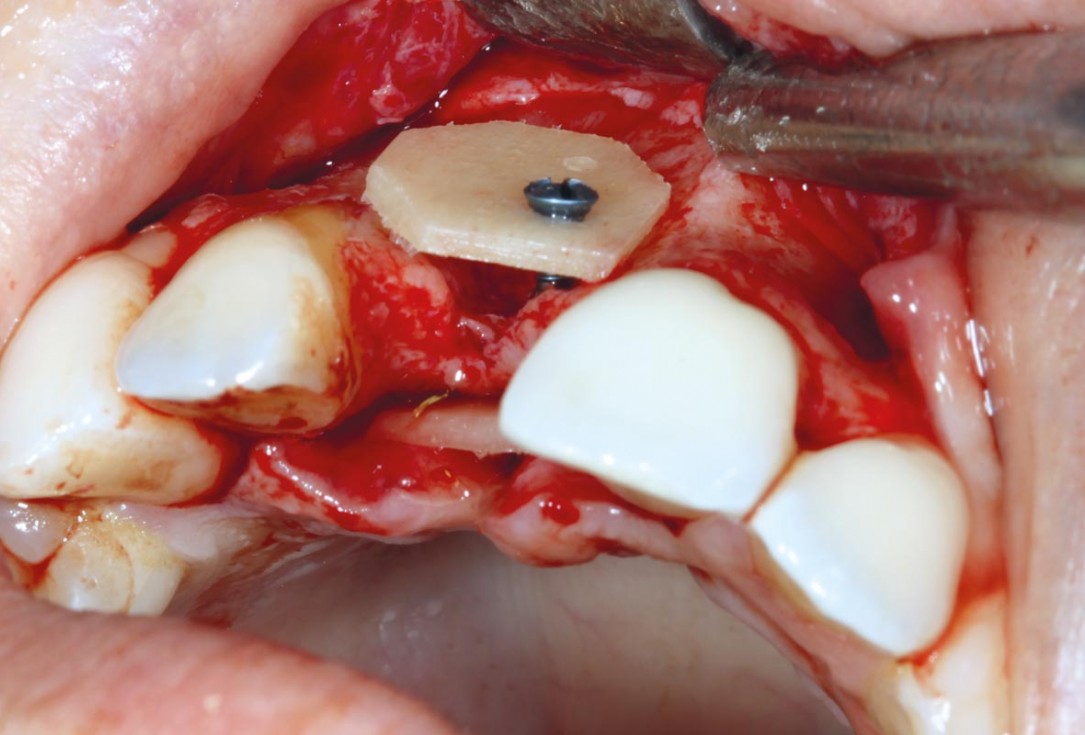

4/11 - Removal of sharp edgesmaxgraft® cortico at combined defect palatally and facially - Dr. K. Höckl